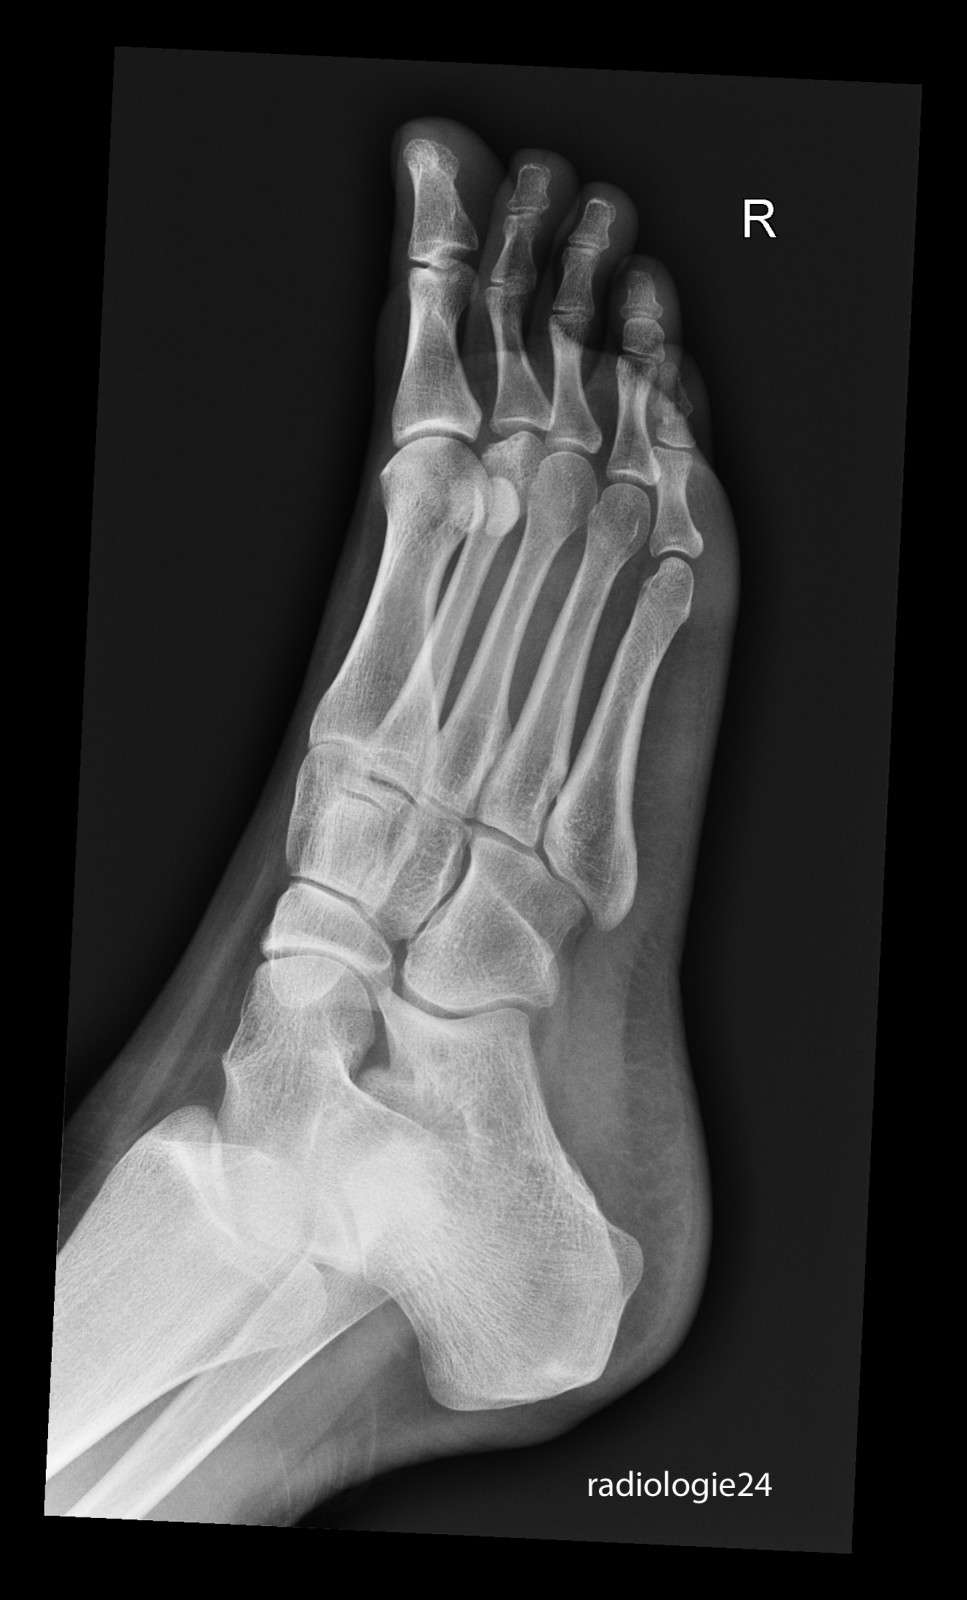

Röntgenfall des Monats November 2017 mit Auflösung

18 jährige Patientin Klinische Angaben: Schmerzen Vorfussbereich. Kein Trauma erinnerlich.

Link zur Auflösung mit ausführlichem Befund

https://www.radiologie24.ch/radiologie-mediathek/roentgenfall_des_monats